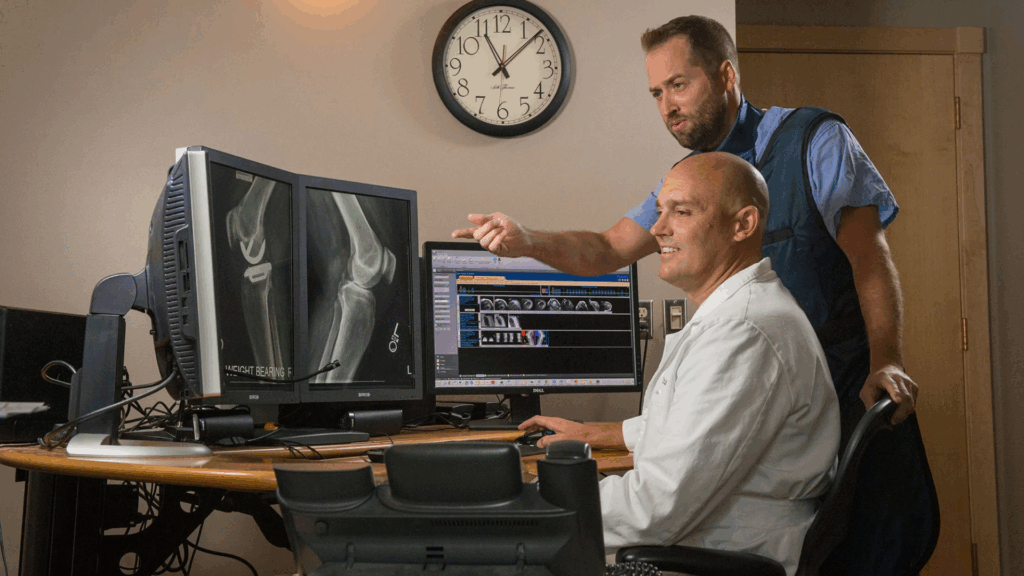

Students passionate about lab work can pursue Bachelor of Medical Laboratory Technology (MLT), focusing on diagnosing diseases through blood, tissue, and fluid testing. Closely related is Bachelor of Radiology and Radiographic Technology, which involves using X-rays, CT scans, and MRIs for imaging. In the growing field of eye care, Bachelor of Optometry opens doors to vision testing, correction, and advanced clinical practice.